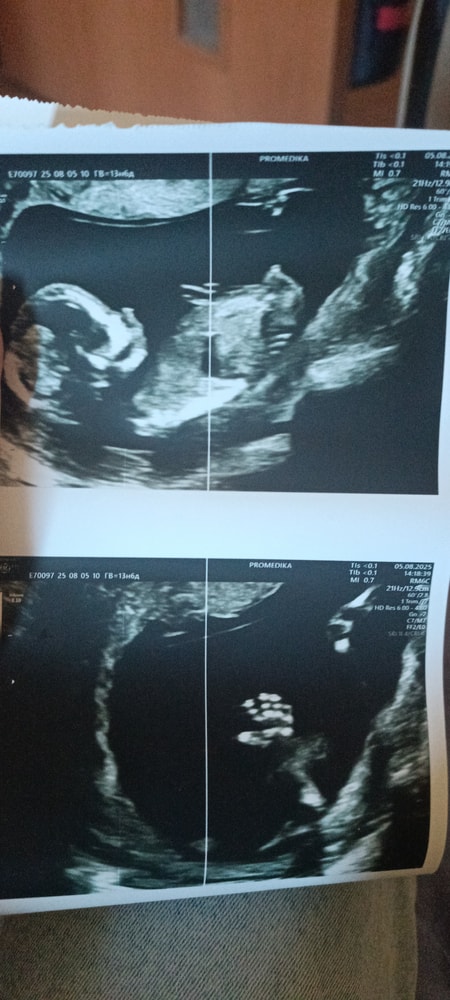

Пол малыша

Девочка вроде ручкой машет)

Анастасия, 14 недель, это фото сейчас

Яна, значит я тоже думаю, что девочка)

Анастасия, ну сейчас тоже так сказали, на скрининге мальчика предположили) сказали через недели 2 придти , вдруг яички опустятся, она так выразилась 😀

Сходила на УЗИ. УЗИ 10 нед в отпуске КЛИНИКА НУРИЕВЫХ